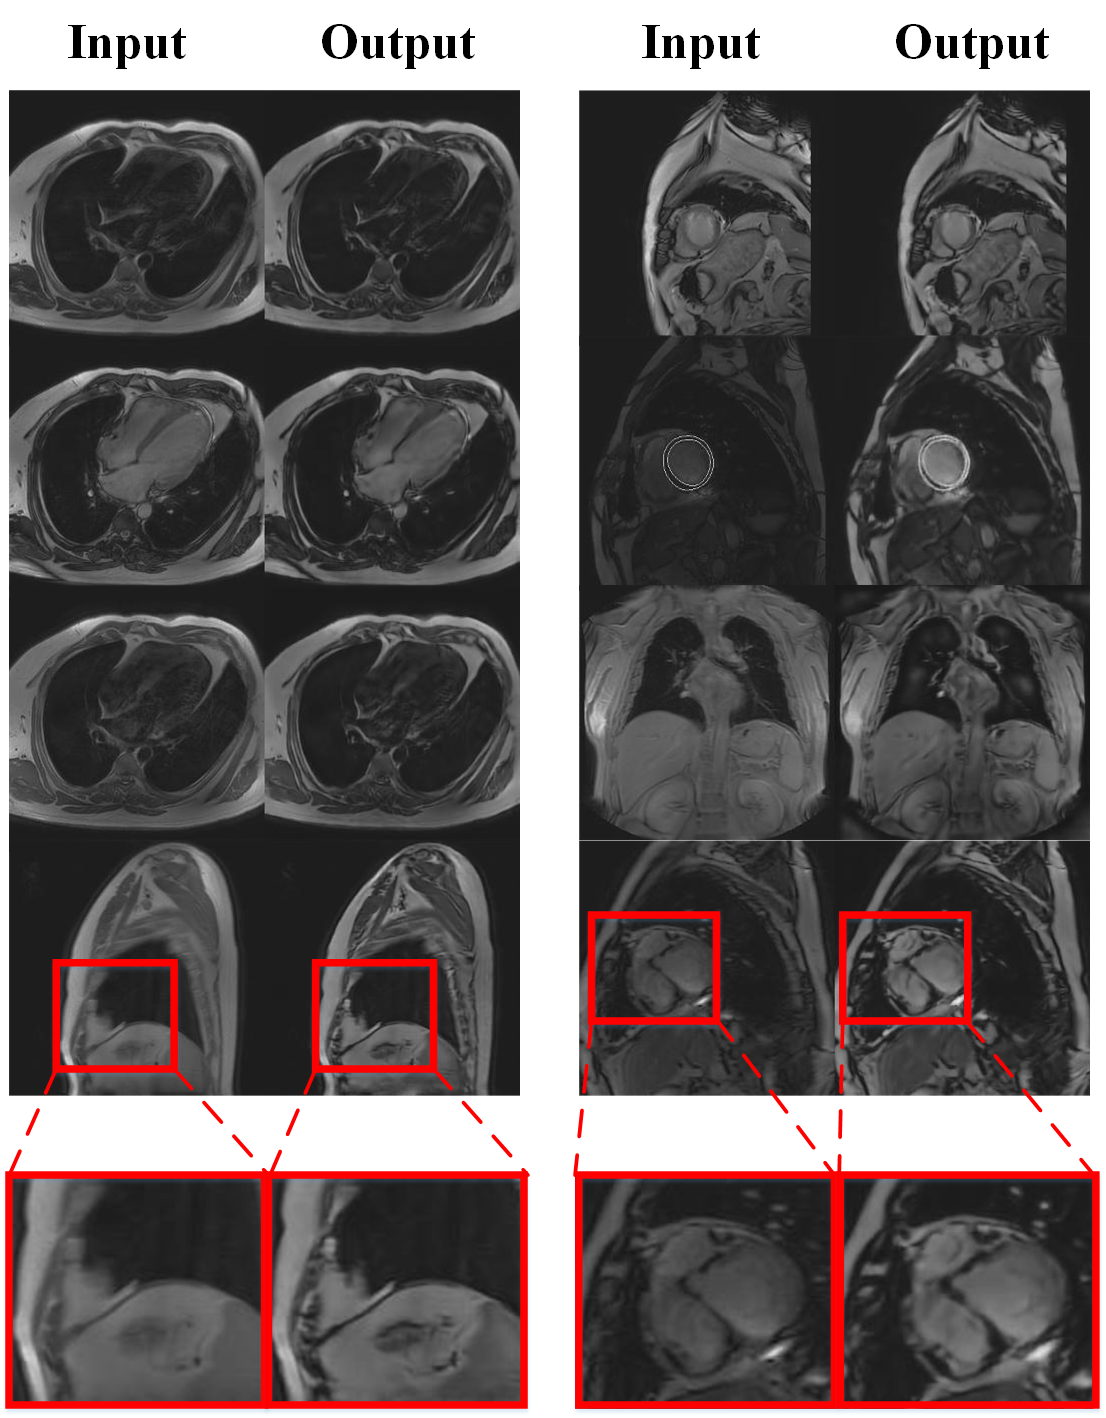

Our work is devoted to correct motion artifact in CMR using deep learning. Specially we use residual network [5] as principle net framework to reconstruct sharp image taking blur image as input and train our model in the adversarial manner [6] to preserve more details which can make output look like more realistic, as shown in Fig. 1.

Fig. 3 illustrates the overall framework of our CMR motion artifact correction system. Given an blur CMR as input, the Generator restores a sharper output.

Suppose there are two image domains: and , referring to image domain with and without (w/o) motion artifact respectively. Analytically, our goal is to restore sharp image given only a motion artifact image , with no information about motion trajectory. In our strategy, we train an Generator to correct from domain to its corresponding in target domain with sharp texture. During the training phase, we introduce the discriminator in an adversarial manner to generate more realistic images.